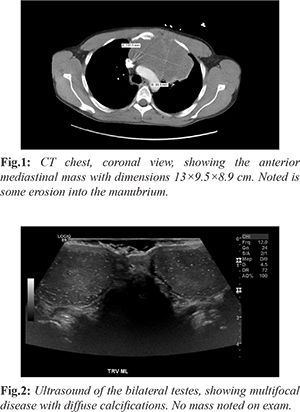

A 33 year old non-smoking man presented to the emergency department in the winter of 2020 with flu-like symptoms and hemoptysis for 1 month. He endorses fever, chills and 10 lb weight loss. He was sent into the emergency department from an urgent care for an abnormal chest x-ray after being worked up for bronchitis. He underwent CT chest, showing large anterior mediastinal mass 13×9.5×8.9 cm, extending towards the left upper lobe [Fig.1]. Mass is also shown to affect the left main pulmonary artery with bony destruction of the left side of the manubrium of the sternum with the tumor appearing to extend into the left anterior chest wall through the 1st left intercostal space anteriorly. The biopsy of the anterior mass was obtained by intervention radiology. Ultrasound showed diffusely abnormal testis, with hyper-vascularization and numerous and diffuse calcifications present throughout both testes [Fig.2]. CT of the abdomen and pelvis was negative for lymphadenopathy or metastatic disease. Tumor markers indicated lactate dehydrogenase (LDH) 1,691 (140-280 U/L), human chorionic gonadotropin (ß-HCG) 0.6 (< 15 ng/mL) and alpha-fetoprotein (AFP) 5.3 (10-20 ng/mL). Biopsy of mediastinal mass resulted in a non-seminomatous germ cell tumor, likely embryonal carcinoma. Immunohistochemical staining was positive for CD30 and PLAP. He was started on chemotherapy with bleomycin, cisplatin, and etoposide.